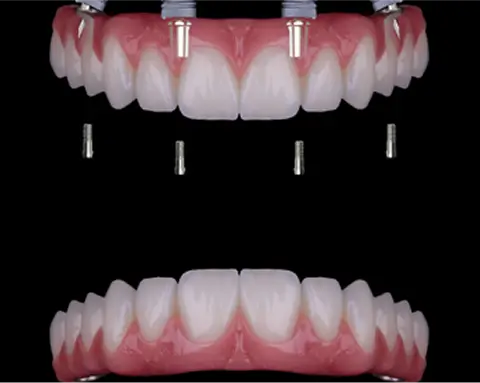

Dientes fijos en 24 horas, estética natural y garantía de por vida en implantes. Especialistas en casos complejos en Madrid.

Sí. En Alejandro Prieto Dental realizamos tratamientos de implantes con carga inmediata, permitiendo al paciente salir con dientes fijos el mismo día. Con estética y funcionalidad casi igual que los dientes definitivos.